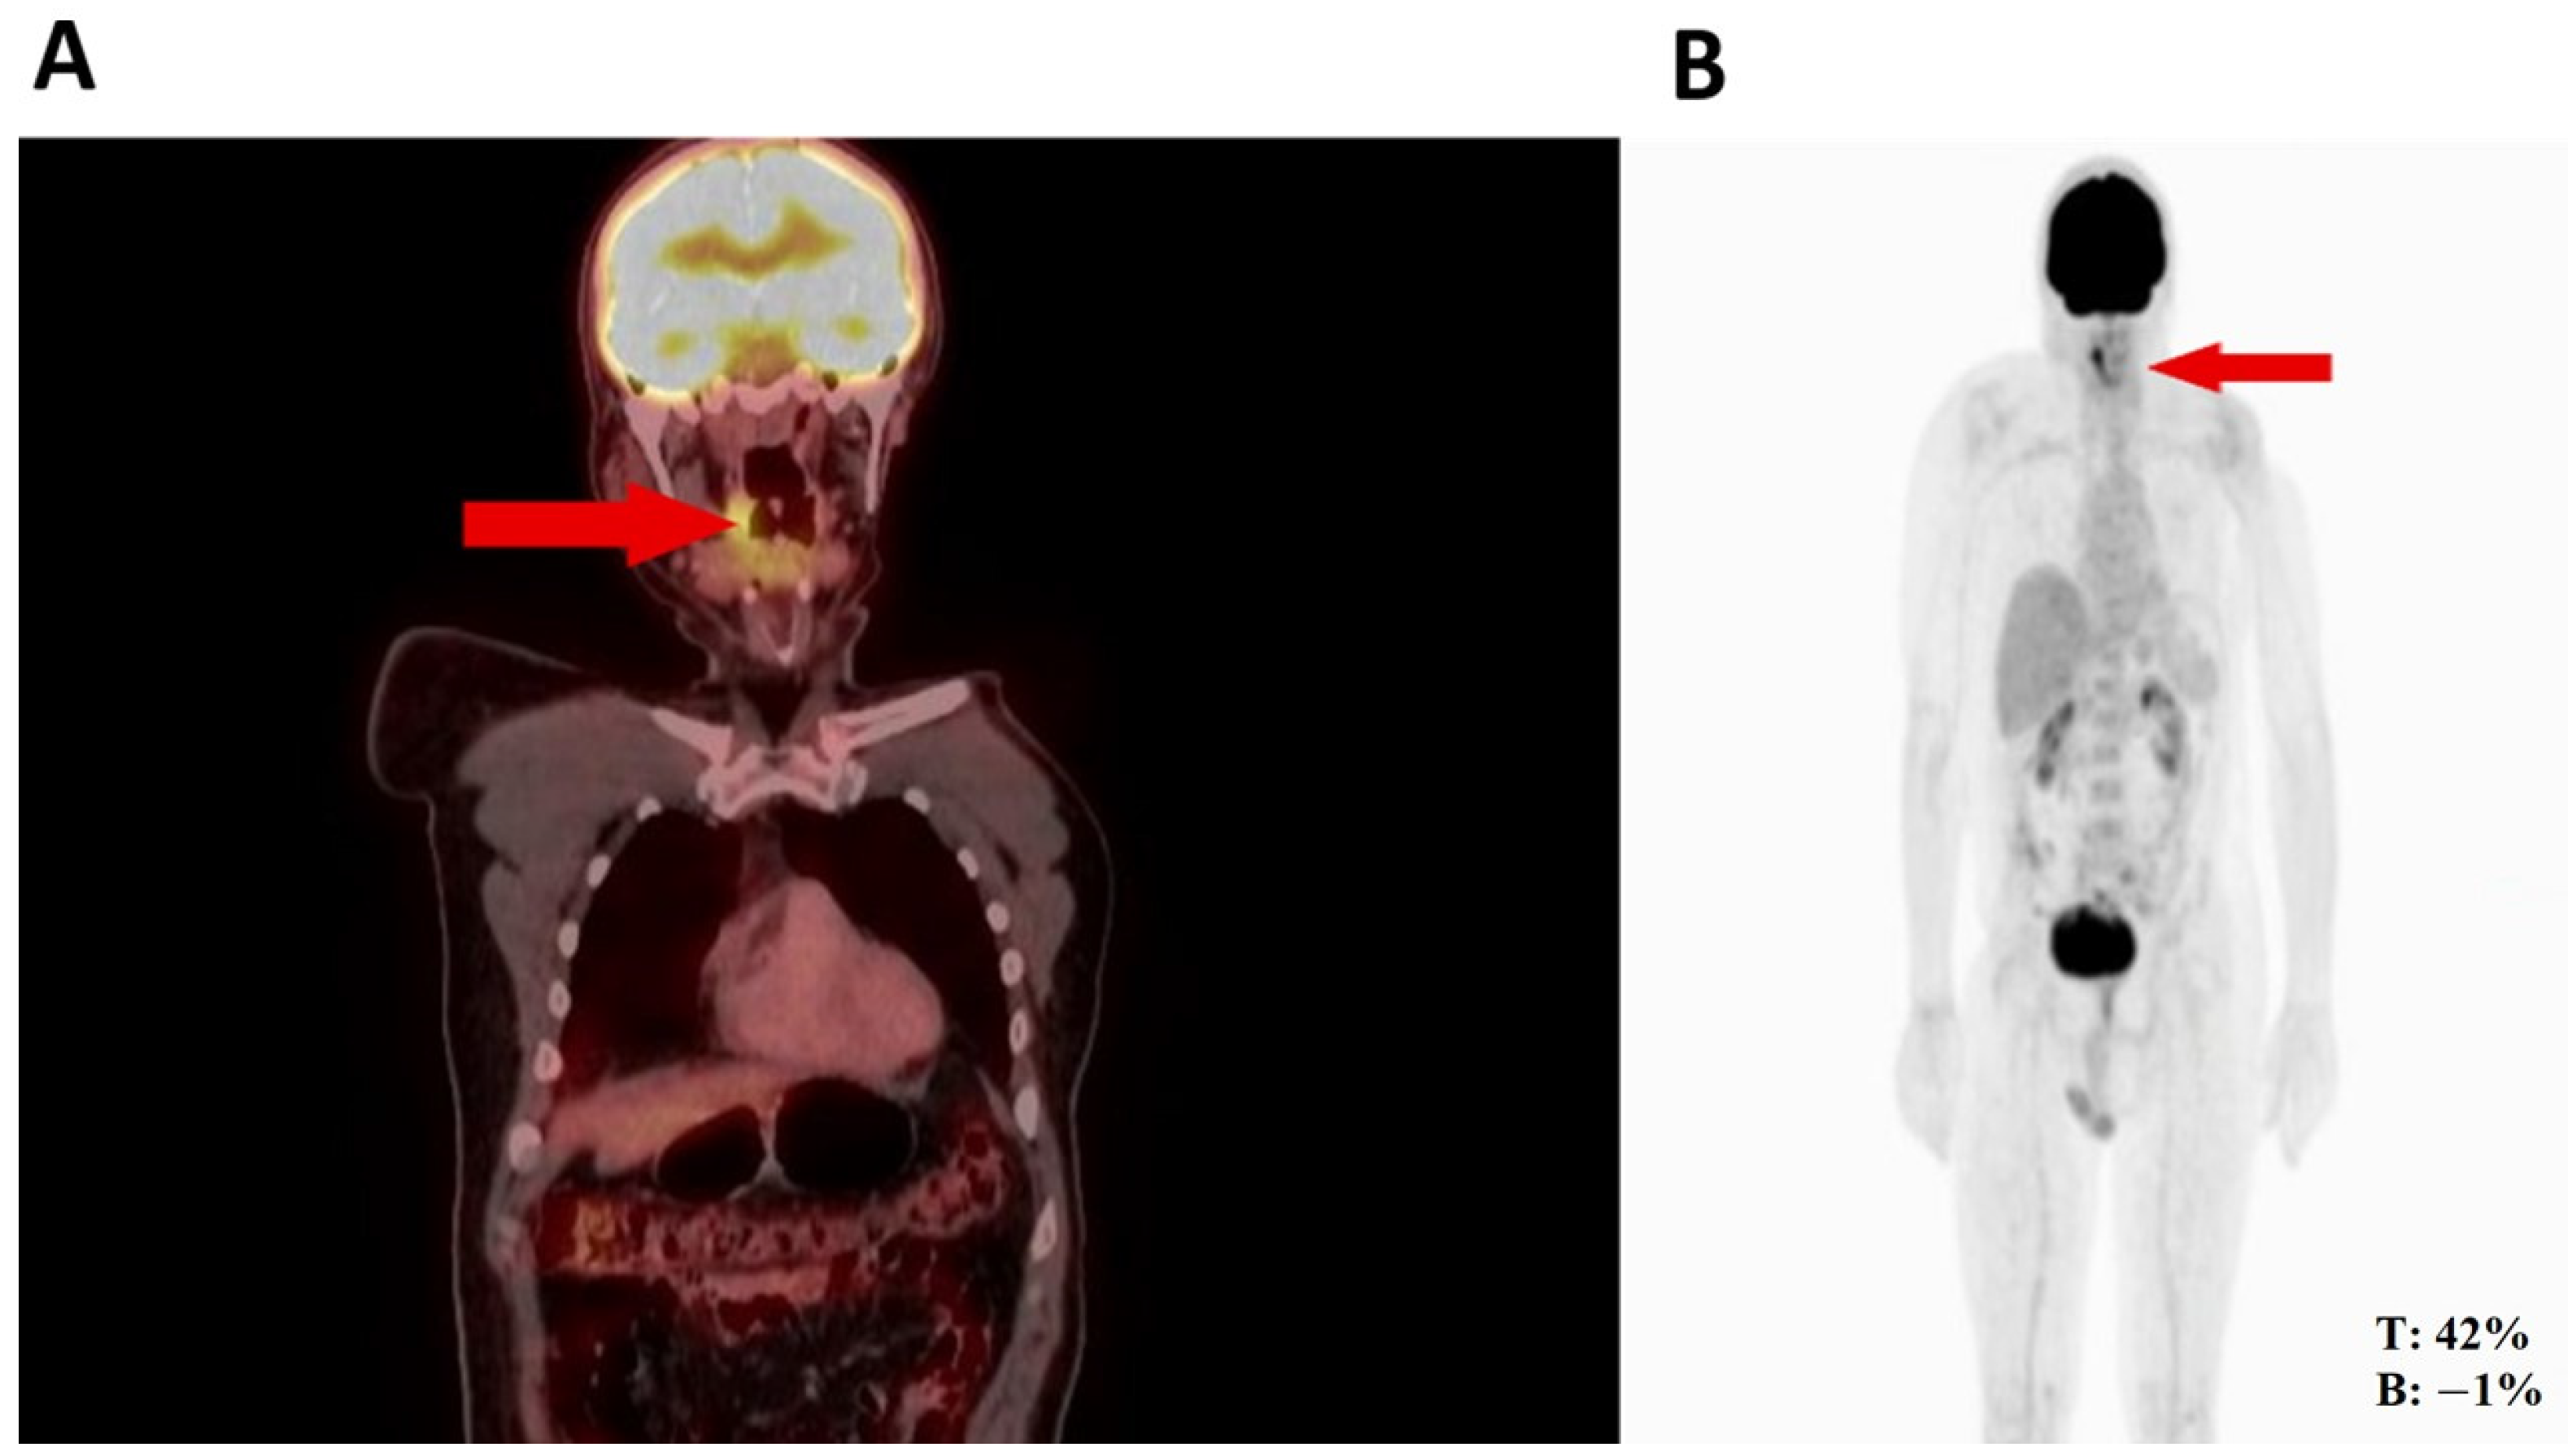

2. Case Report